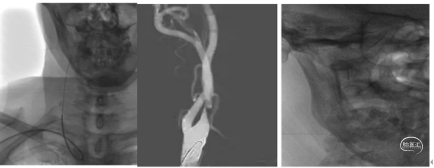

8Fguiding到达C1段支撑070银蛇中间导管裸奔边上行边抽吸,抽出部分血栓,造影显示到血流达到C6段。

术中边推进导管边抽吸,抽出部分血栓,造影显示到血流达到C6段。

支架取栓:

1、微导管到位:微导丝通过M1段艰涩困难,再次偿试通过M1段到达M2。携带微导管到达M2段,微导管造影显示远端有正向血流,在真腔内。下图1

2、支架释放:通过027微导管释放6X30mm 通桥蛟龙支架,静置5分钟后微造影,大脑中未显影,未见首过效应考虑血栓负荷较大。大脑前有血流。下图2